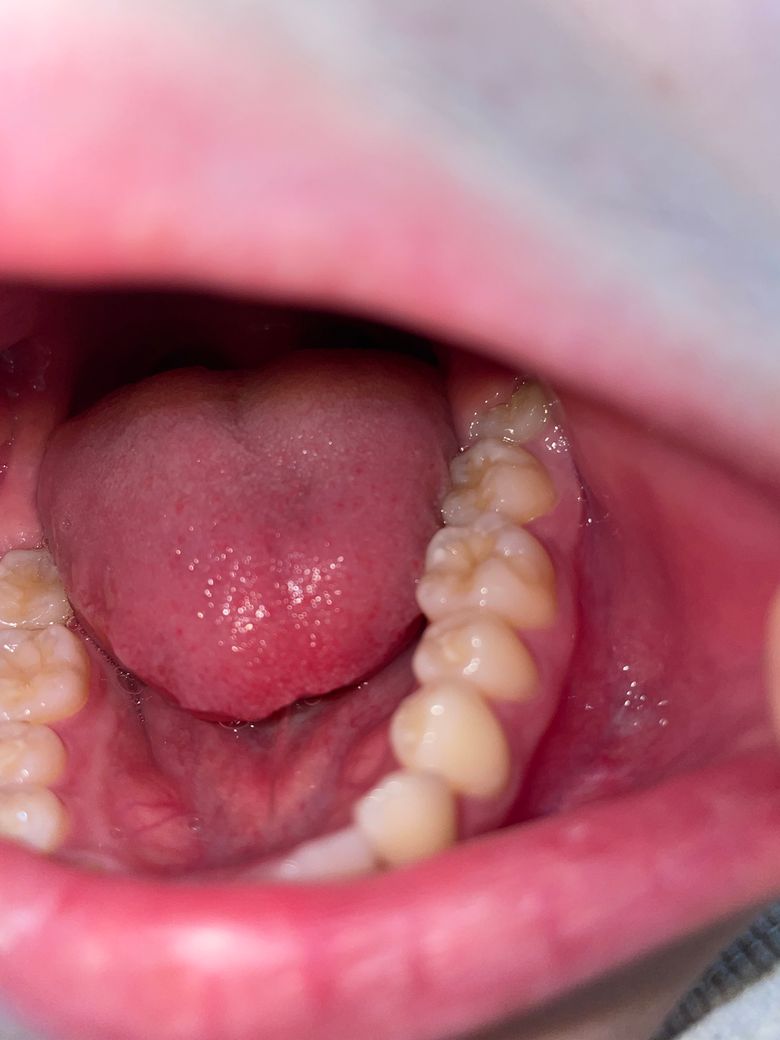

충치일까요?? 구멍은 뭔가요? 치료하려면 많이 아플까요ㅠ

충치일거같긴한데… 구멍도 있는거같아서요ㅠㅠㅠ차가운거 먹었을때만 좀 시려요 ..금데 한 1-2초 후에 바로 괜찮아집니다..!! 근데 제가 치과를 목요일쯤에 갈수있을거같은데 그 사이 더 심해지진 않겠죠 ㅠㅠ? 혹시 이 충치 치료려면 얼마나 아플까요..?ㅠㅠㅠ

어금니에 충치가 보입니다. 따라서 해당 부위의 치료가 필요할 것으로 보이나 현재 차가운것에 시린 증상은 해당 치아로 인한 것인지 다른 치아에도 문제가 있는지는 치과 방문 후 검진을 받아보셔야 합니다. 대부분 충치는 진행속도가 크지 않으므로 단순히 일주일 정도 지나서 치과를 방문하더라도 큰 차이는 없습니다. 물론 가급적이면 빨리 치과를 방문하는 것이 좋습니다.

많이 심해보이지는 않지만 간혹 보기보다 충치가 더 많이 진행된 경우도 종종 있습니다.

충치는 있으실꺼 같긴합니다. 하지만 저기 구멍뚤린건 원래 치아 모양이 그렇게 생긴거에요. 충치 깊이는 엑스레이 사진등을 찍어보시고 판단해야되니 치과에 가셔서 검진을 받아보세요.

첫번째 큰어금니의 작은 충치일 가능성이 있습니다.